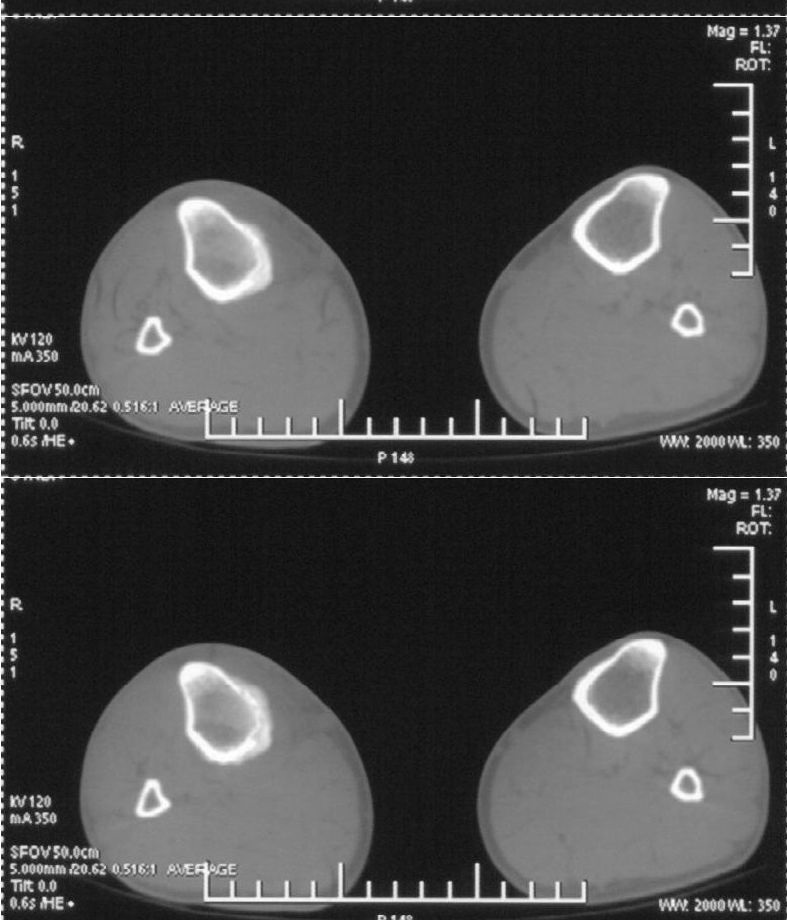

男,42岁。4个月前钢筋钝伤右侧小腿部,当时因无明显外伤,未引起重视。一周后因受伤腿部疼痛,发现肿胀,随后到当地医院进行检查(2008年4月16日)。因未发现骨质异常未引起重视,仅仅进行口服抗生素治疗处理。经过一段时间治疗但未见明显治疗效果在5月29日又进行x线检查,发现有胫骨密度上段密度增高,又进行抗炎治疗,仍未见效果。又在7月3日进行x线检查,仍然报告有胫骨上端密度增高,并建议ct检查。以下是相关检查结果:

髓腔密度呈絮状增高,胫骨上端内侧可见层状骨膜反应,考虑骨髓炎.

髓腔密度呈絮状增高,胫骨上端内侧可见层状骨膜反应,肌间隙模糊,考虑骨髓炎.